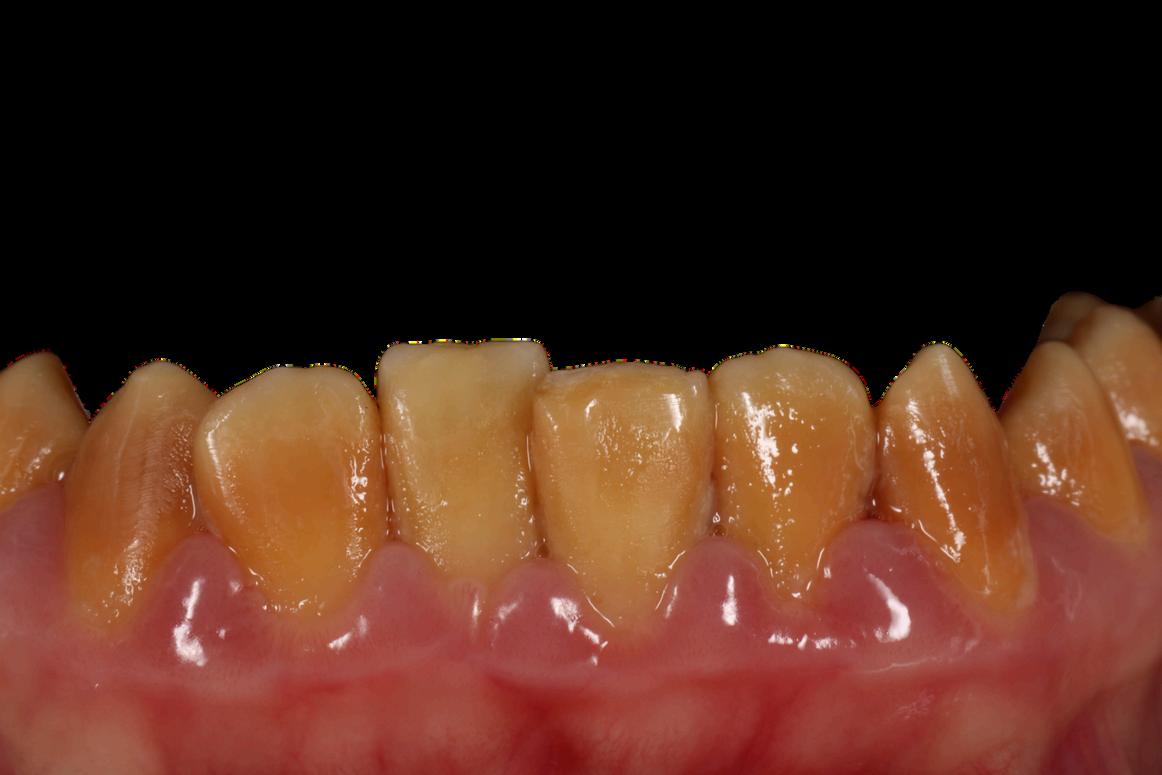

Es un defecto relacionado a la poca mineralización de los tejidos duros de los primeros molares permanentes e incisivos centrales inferiores y/o superiores, los cuales tienden a formarse en el mismo período de tiempo, pudiera estar relacionado algún otro diente en la cavidad bucal pero es poco frecuente y se da de forma aleatoria entre caninos y premolares

Este defecto se define como un problema cualitativo del esmalte, es decir, su esmalte tiene baja calidad mineral

El color de la lesión solo indica mayor profundidad del defecto, así tenemos que mientras la mancha es de color crema, menos profundo es el defecto y mejor pronóstico tiene Por el contrario, mientras la mancha o lesión tiene un color mas oscuro hacia el ocre o marrón, mayor el daño a profundidad y por consiguiente peor pronóstico, el tratamiento debe ser mas invasivo, menos longevo, de mayor costo y muchas veces menos indicado o aceptado

Las posibles causas son enfermedades crónicas como problemas renales, acidosis tubular, nefrocalcinosis, enfermedades nutricionales, alergias y amigdalitis recurrentes, uso frecuente de esteroides y antihistamínicos, así como cualquier afección metabólica y nutricional localizadas en los tres (3) primeros años de vida

La Hipomineralización molar incisivo está muy relacionada a la Condición Celíaca y es erróneamente tratada como caries

Cursa con mucha hiper sensibilidad dentinaria, fracturas del esmalte, dolor, mala higiene bucal, pérdida de estructura dentaria, pobre estética, desinserción social, baja auto estima, auto imagen y deserción escolar.